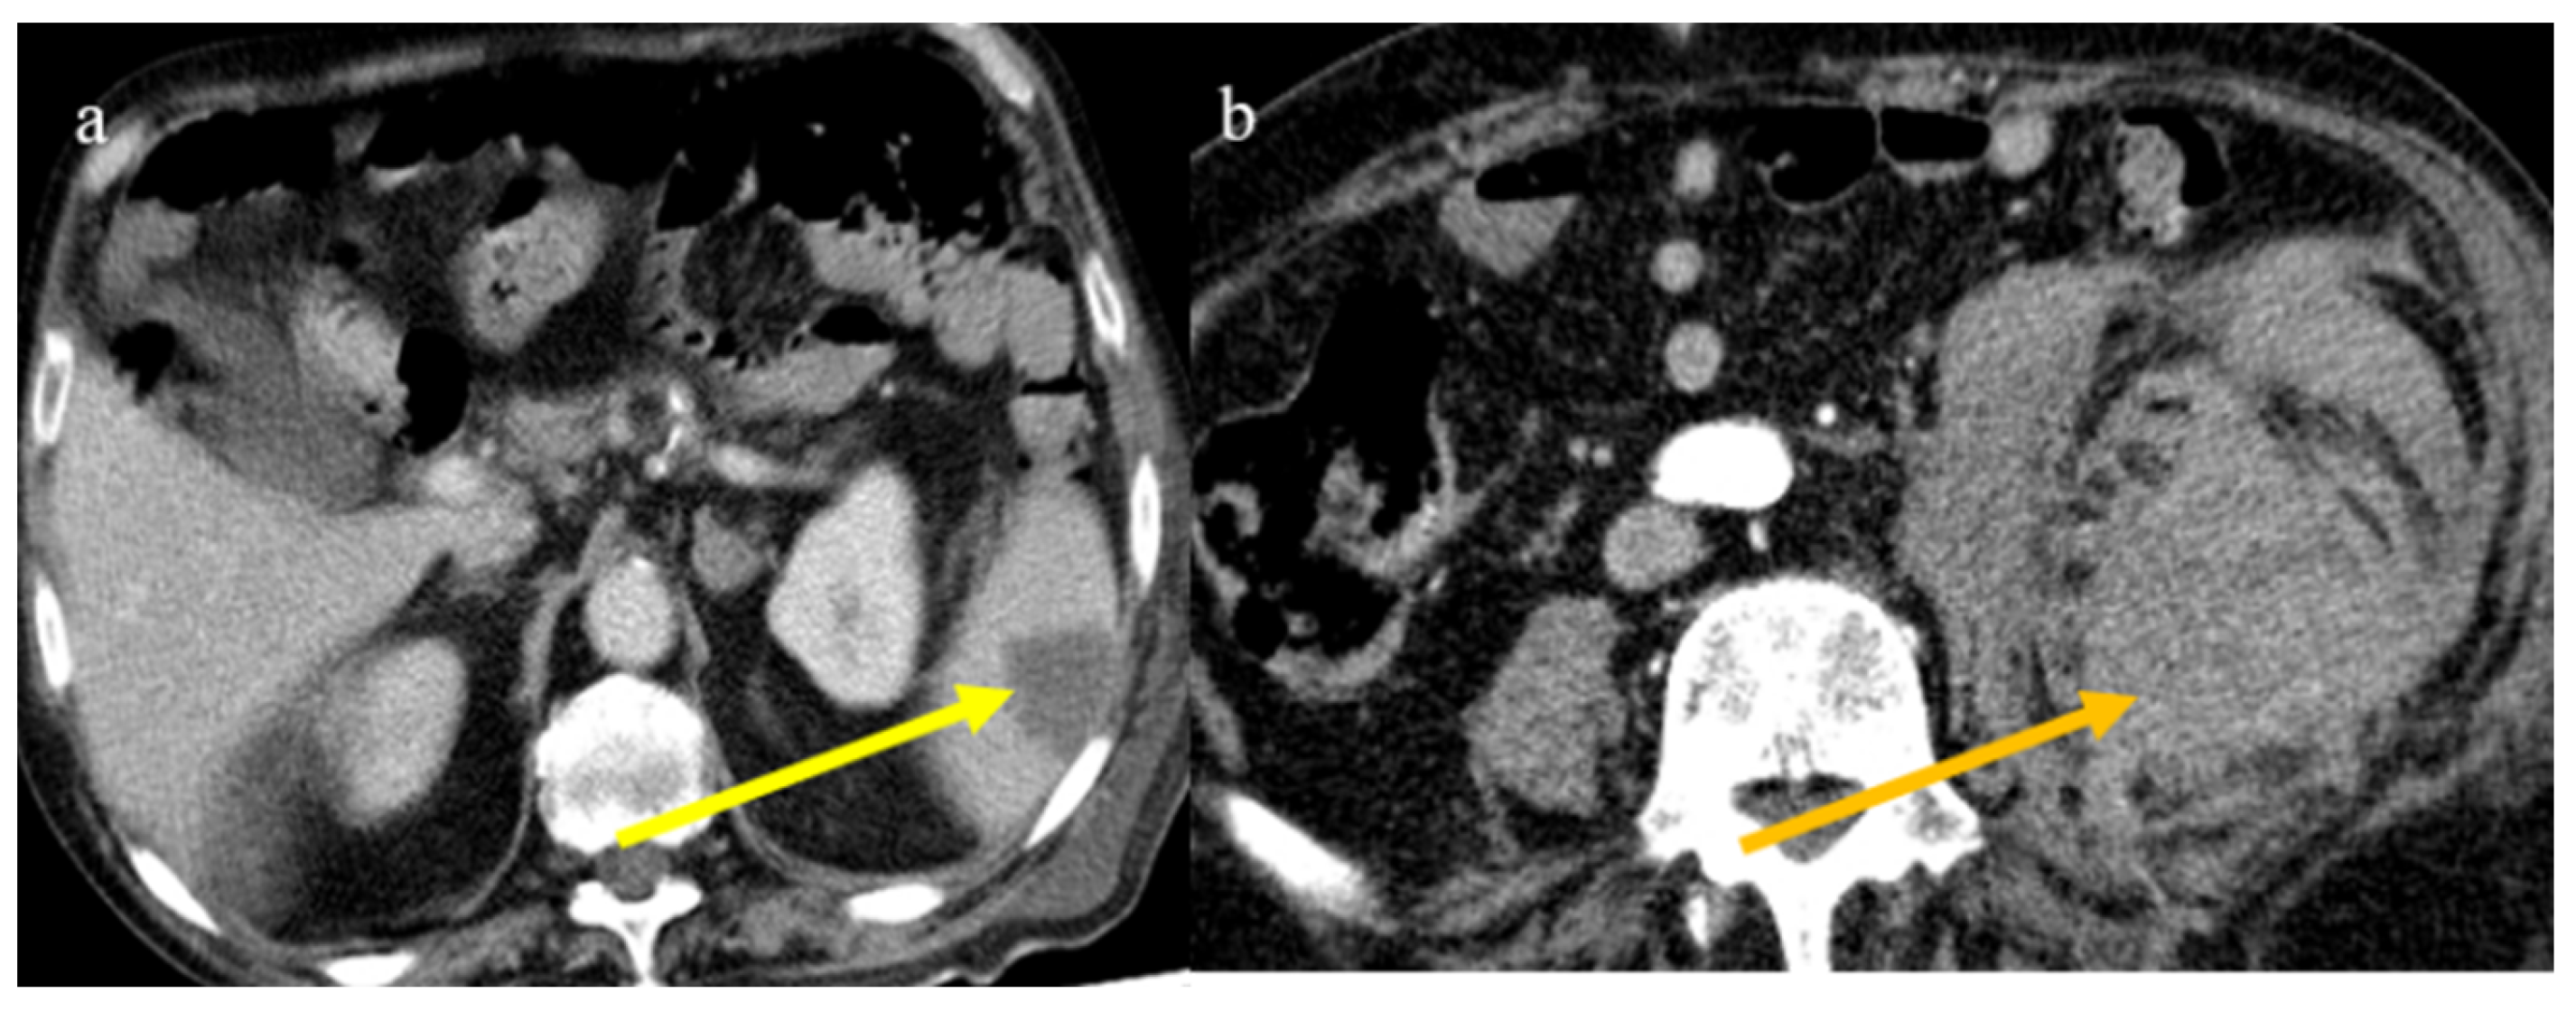

4.1. Small Bowel Ischemia and Ischemic Colitis

4.2. Splenic and Renal Infarction

- Bonaffini, P.A.; Franco, P.N.; Bonanomi, A.; Giaccherini, C.; Valle, C.; Marra, P.; Norsa, L.; Marchetti, M.; Falanga, A.; Sironi, S. Ischemic and hemorrhagic abdominal complications in COVID-19 patients: Experience from the first Italian wave. Eur. J. Med. Res. 2022, 27, 1–9. [Google Scholar] [CrossRef]

- Peshevska-Sekulovska, M.; Boeva, I.; Sekulovski, M.; Zashev, M.; Peruhova, M. Gastrointestinal Ischemia—Stumbling Stone in COVID-19 Patients. Gastroenterol. Insights 2022, 13, 206–217. [Google Scholar] [CrossRef]

- Norsa, L.; Bonaffini, P.A.; Caldato, M.; Bonifacio, C.; Sonzogni, A.; Indriolo, A.; Valle, C.; Furfaro, F.; Bonanomi, A.; Franco, P.N.; et al. Intestinal ischemic manifestations of SARS-CoV-2: Results from the ABDOCOVID multicentre study. World J. Gastroenterol. 2021, 27, 5448–5459. [Google Scholar] [CrossRef]

- Singh, B.; Kaur, P. COVID-19 and acute mesenteric ischemia: A review of literature. Hematol. Transfus. Cell Ther. 2020, 43, 112–116. [Google Scholar] [CrossRef]

- Fathy, A.; Rizk, A.; Elnekeidy, A.; Gharraf, H.S.; Abdelgawad, M.S.; Samir, A. Imaging of COVID-19 vasculopathy from head to toe: Egyptian collective experience after 2 years of the pandemic. Egypt. J. Radiol. Nucl. Med. 2022, 53, 1–21. [Google Scholar] [CrossRef]

- Bhayana, R.; Som, A.; Li, M.D.; Carey, D.E.; Anderson, M.A.; Blake, M.A.; Catalano, O.; Gee, M.S.; Hahn, P.F.; Harisinghani, M.; et al. Abdominal Imaging Findings in COVID-19: Preliminary Observations. Radiology 2020, 297, E207–E215. [Google Scholar] [CrossRef]

- Caruso, D.; Zerunian, M.; Pucciarelli, F.; Lucertini, E.; Bracci, B.; Polidori, T.; Guido, G.; Polici, M.; Rucci, C.; Iannicelli, E.; et al. Imaging of abdominal of abdominal complications of COVID-19 infection. BJR Open 2021, 2, 20200052. [Google Scholar] [CrossRef]

- Ojha, V.; Mani, A.; Mukherjee, A.; Kumar, S.; Jagia, P. Mesenteric ischemia in patients with COVID-19: An updated systematic review of abdominal CT findings in 75 patients. Abdom. Imaging 2021, 47, 1565–1602. [Google Scholar] [CrossRef]

- Boraschi, P.; Giugliano, L.; Mercogliano, G.; Donati, F.; Romano, S.; Neri, E. Abdominal and gastrointestinal manifestations in COVID-19 patients: Is imaging useful? World J. Gastroenterol. 2021, 27, 4143–4159. [Google Scholar] [CrossRef]

- Keshavarz, P.; Rafiee, F.; Kavandi, H.; Goudarzi, S.; Heidari, F.; Gholamrezanezhad, A. Ischemic gastrointestinal complications of COVID-19: A systematic review on imaging presentation. Clin. Imaging 2020, 73, 86–95. [Google Scholar] [CrossRef] [PubMed]

- Gupta, A.; Sharma, O.; Srikanth, K.; Mishra, R.; Tandon, A.; Rajput, D. Review of Mesenteric Ischemia in COVID-19 Patients. Indian J. Surg. 2022, 85, 313–321. [Google Scholar] [CrossRef]

- Reginelli, A.; Genovese, E.; Cappabianca, S.; Iacobellis, F.; Berritto, D.; Fonio, P.; Coppolino, F.; Grassi, R. Intestinal Ischemia: US-CT findings correlations. Crit. Ultrasound J. 2013, 5, S7. [Google Scholar] [CrossRef]